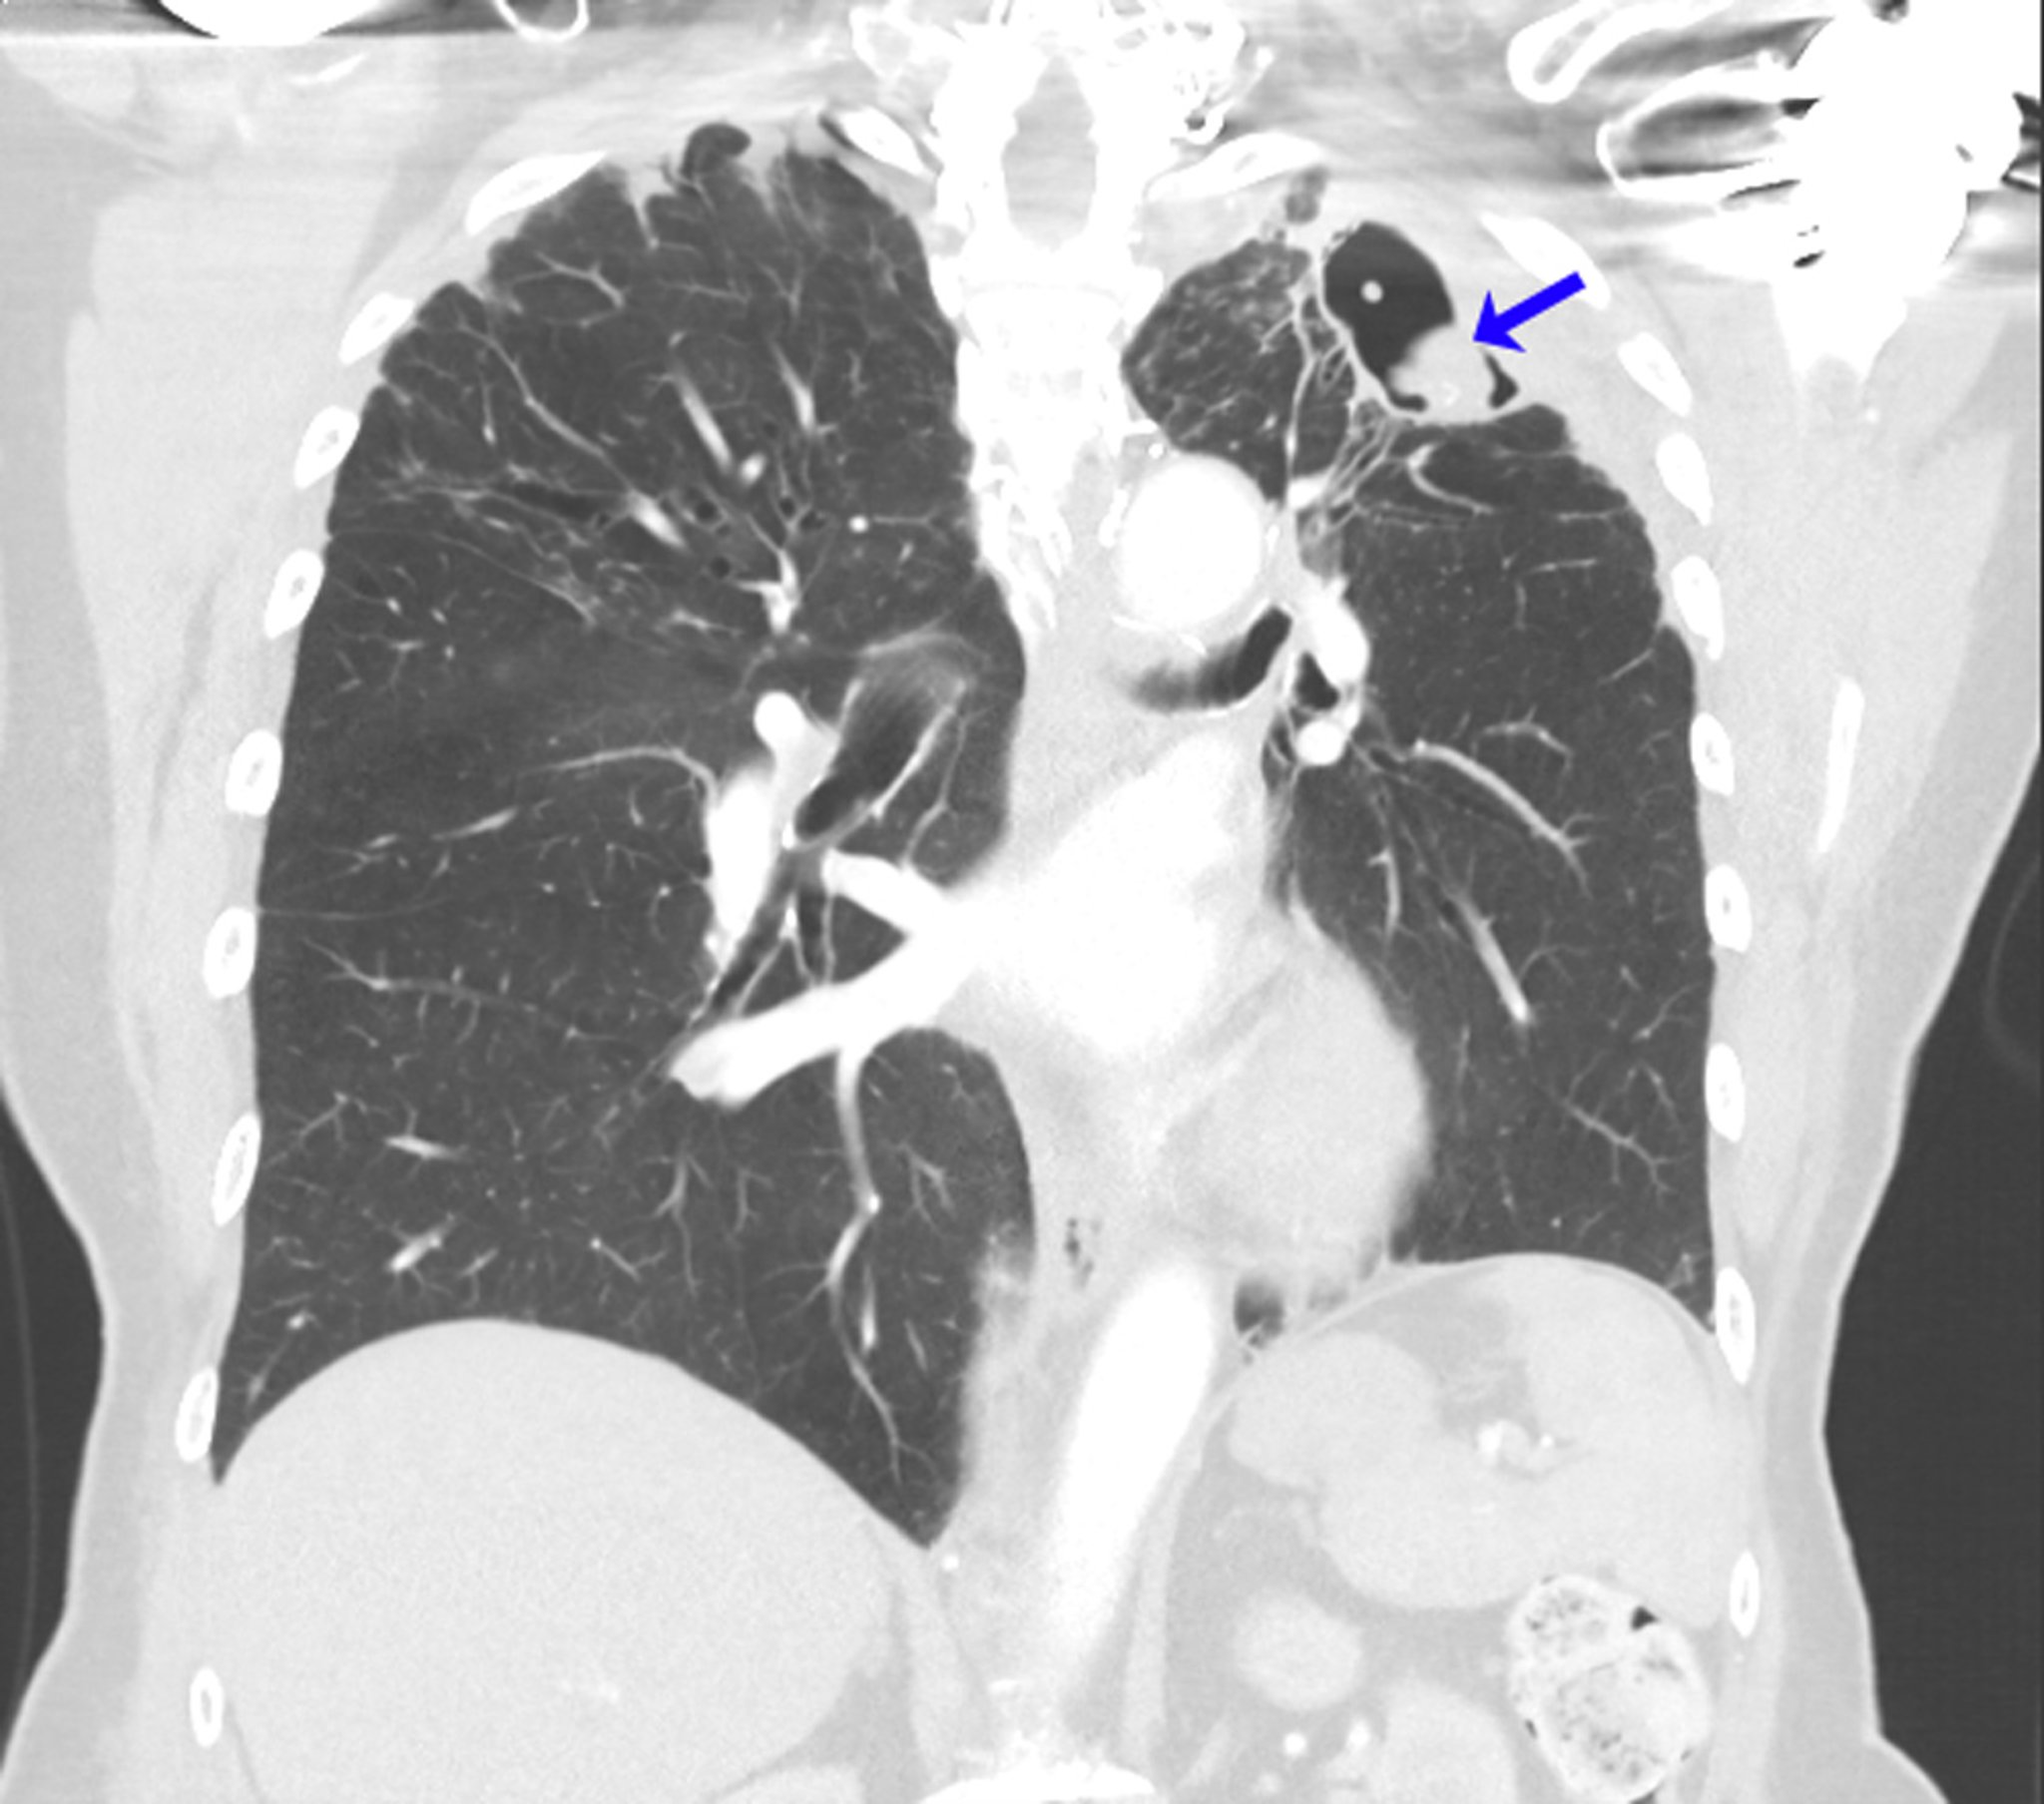

Rezidivierendes Aspergillom

Diese CT-Aufnahme zeigt die Lunge einer Person mit einer allergischen bronchopulmonalen Aspergillose in der Anamnese im Zusammenhang mit Asthma. Nach einer Aspergillom-Lobektomie des linken Oberlappens entwickelte sich ein rezidivierendes Myzetom an der linken Lungenspitze (Pfeil).

Image courtesy of Paschalis Vergidis, MD, MSc.